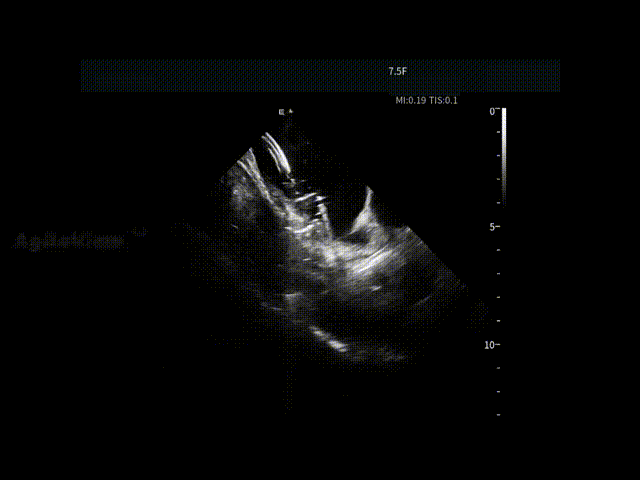

▶【术后影像复核,安全闭环确认】

消融完成后,张曦教授再次使用ICE对心包区域进行系统扫查,确认术后腔内情况稳定,未见异常变化。整台消融流程在清晰影像指引下顺利完成,消融时间约53-60分钟。术中患者耐受良好,术后恢复平稳,未见相关并发症。

术后心包-积液无增加